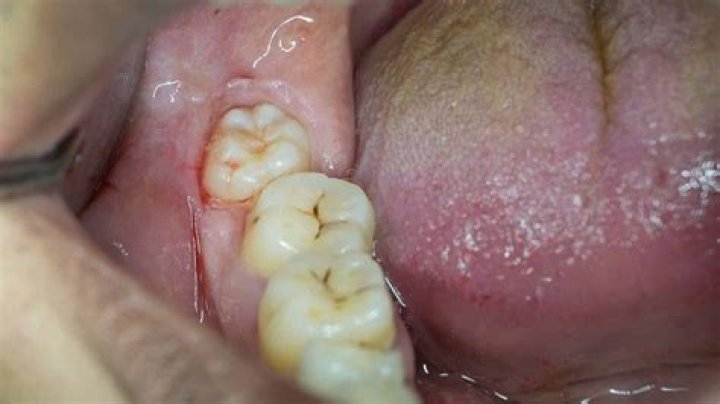

Wisdom teeth usually emerge sometime between the ages of 17 and 25. Some people have wisdom teeth that emerge without any problems and line up with the other teeth behind the second molars. In many cases, however, the mouth is too crowded for third molars to develop normally.

Wisdom teeth normally start to erupt between the ages of 17 and 25. However, the process does not happen at the same pace for everyone. In fact, it can take years for the wisdom teeth to fully emerge through the gums or they may never erupt at all.

What does wisdom teeth coming in feel like?

Even if your wisdom teeth emerge through your gums normally, they can cause you to feel various mild symptoms. You might experience some mild pain, the feeling of pressure in your mouth or jaw, or a dull throbbing sensation in your gums, close to the opening of your throat or in your jaw bone which is nearby.